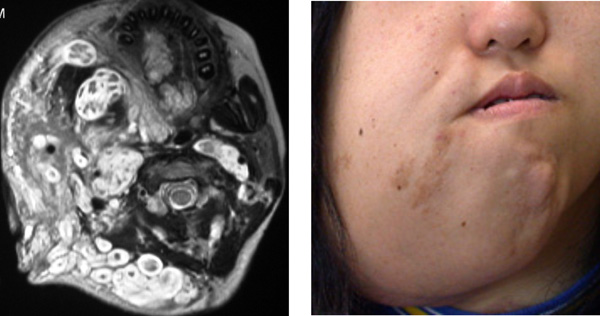

神経線維腫は、神経を取り囲んで保護する組織層である神経鞘で発生する腫瘍です。 PN は最も複雑なタイプの神経線維腫です。これらは通常、神経の束または単一の神経の長い部分に影響を与えます。

PN は、脳と脊髄以外の体のどの部分でも発生する可能性があります。それらは皮膚の表面近くに形成される場合もあれば、体内のより深い部分に形成される場合もあります。

皮膚の表面近くの PN は、目立つしこりを引き起こす場合があります。このしこりは時間の経過とともにかなり大きくなる可能性があります。その上の皮膚は周囲の皮膚よりも色が濃いか、厚い場合があります。

PN が体内のより深くまで成長した場合、目立ったしこりは生じない場合があります。